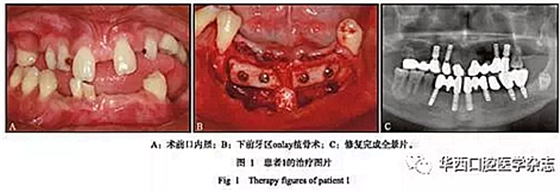

患者1,男,17歲,口內(nèi)檢查示:12、13、14、15、17牙,22、23、24、25、27牙,31、32、33、35、36、37牙,41、42、43、44牙缺失;52、53、63、65、81、 82乳牙滯留;38牙埋伏阻生。11、21牙畸形異位,間隙較大,左上頜側(cè)切牙區(qū)及下頜前牙區(qū)牙槽骨極窄,呈刃狀,右上頜前磨牙區(qū)骨量較窄,腭側(cè)骨缺損明顯(圖1A)。

1)分別行右上頜前磨牙區(qū)及下前牙區(qū)onlay植骨術(shù),下頜前牙區(qū)取頦部自體骨塊(圖1B),避免開辟第二術(shù)區(qū),減輕患者痛苦,術(shù)中拔除滯留乳牙52、53、81、82;

2)避開22、23牙位點(diǎn),于24牙位點(diǎn)行經(jīng)牙槽嵴頂上頜竇提升術(shù)同期植入種植體1枚,行21—24牙(三單位)烤瓷橋修復(fù),降低手術(shù)難度,減小手術(shù)風(fēng)險(xiǎn),術(shù)中拔除滯留乳牙 63、65;

3)正畸轉(zhuǎn)診評(píng)估后,因牽引易導(dǎo)致11、21牙松動(dòng)脫落,故行烤瓷冠修復(fù)關(guān)閉其間隙,而患者為低笑線型患者,降低了美學(xué)風(fēng)險(xiǎn);4)12、13、24、25、31、33、35、36、41、43牙位共植入10枚種植體;5)利用16、47、46牙穩(wěn)定的咬合關(guān)系,分階段進(jìn)行永久修復(fù),根據(jù)右側(cè)天然恒牙正常的咬合高度修復(fù)左側(cè)后牙,左側(cè)后牙修復(fù)完成后再進(jìn)行右側(cè)后牙修復(fù),最后進(jìn)行前牙修復(fù)。分階段的修復(fù)方式降低了修復(fù)復(fù)雜性,避免了咬合重建,患者肌肉關(guān)節(jié)適應(yīng)良好,最終完成上部修復(fù)(圖1C)。